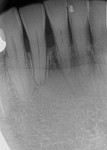

A comprehensive periodontal examination revealed generalized 3 mm to 4 mm horizontal bone loss with minimal probing depths, mobility, and furcation defects. Generalized 3 mm to 4 mm gingival recession with a minimum 2 mm width of attached gingiva was measured at all teeth and sites except the buccal surface of tooth No. 24, which had 6 mm of gingival recession, probing depths between 1 mm and 2 mm at the buccal and lingual aspects, 0 mm of attached gingiva, bleeding on probing, and plaque accumulation (Figure 1). Tension placed on the mandibular frenum caused blanching of the gingival margin of No. 24.

On the day of surgery, after local anesthesia was administered, the mandibular frenum was removed and a partial-thickness flap was reflected along the mucogingival border starting at tooth No. 25 distal and ending at tooth No. 24 distal; the partial-thickness flap was apically extended using sharp dissection with a #15C blade. Upon reflection, a suspected horizontal root fracture was noted in the apical third of tooth No. 24 (Figure 2). The fracture line was filled with a calcified material that could not be penetrated with the #23 explorer. The root subsequently was debrided and root-planed. A 10-mm x 15-mm free gingival graft obtained from the upper right palate was trimmed to cover the buccal defect at No. 24 and sutured with 6-0 polypropylene sutures (Figure 3). The donor site was sutured with 4-0 chromic gut in conjunction with use of an acrylic surgical stent.

Periodontal examination 8 weeks postoperatively (Figure 5) revealed regeneration of the keratinized tissue, elimination of the frenal pull, and a 1 mm decrease in recession at tooth No. 24. Probing depths remained between 1 mm and 2 mm without bleeding on probing. Radiographic analysis (Figure 6) verified a lack of periapical radiolucency or other pathology associated with No. 24 and reinforced the fact that mucogingival treatment did not affect tooth vitality or the healed horizontal fracture site.